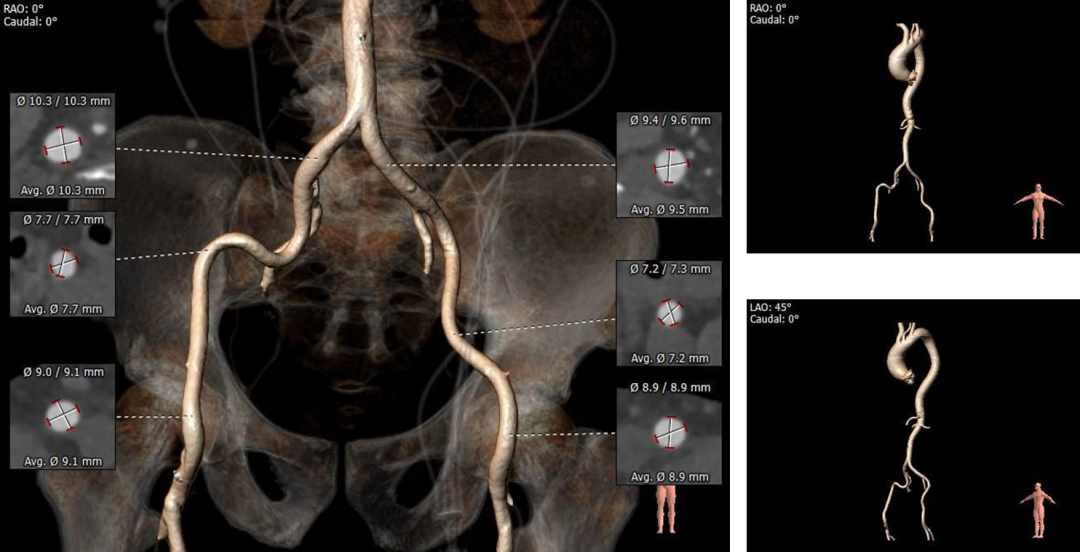

5. 双侧股髂动脉未见明显迂曲,右髂走行略微扭曲,管腔内径可,整体血管条件良好。

外周血管及主动脉弓解剖